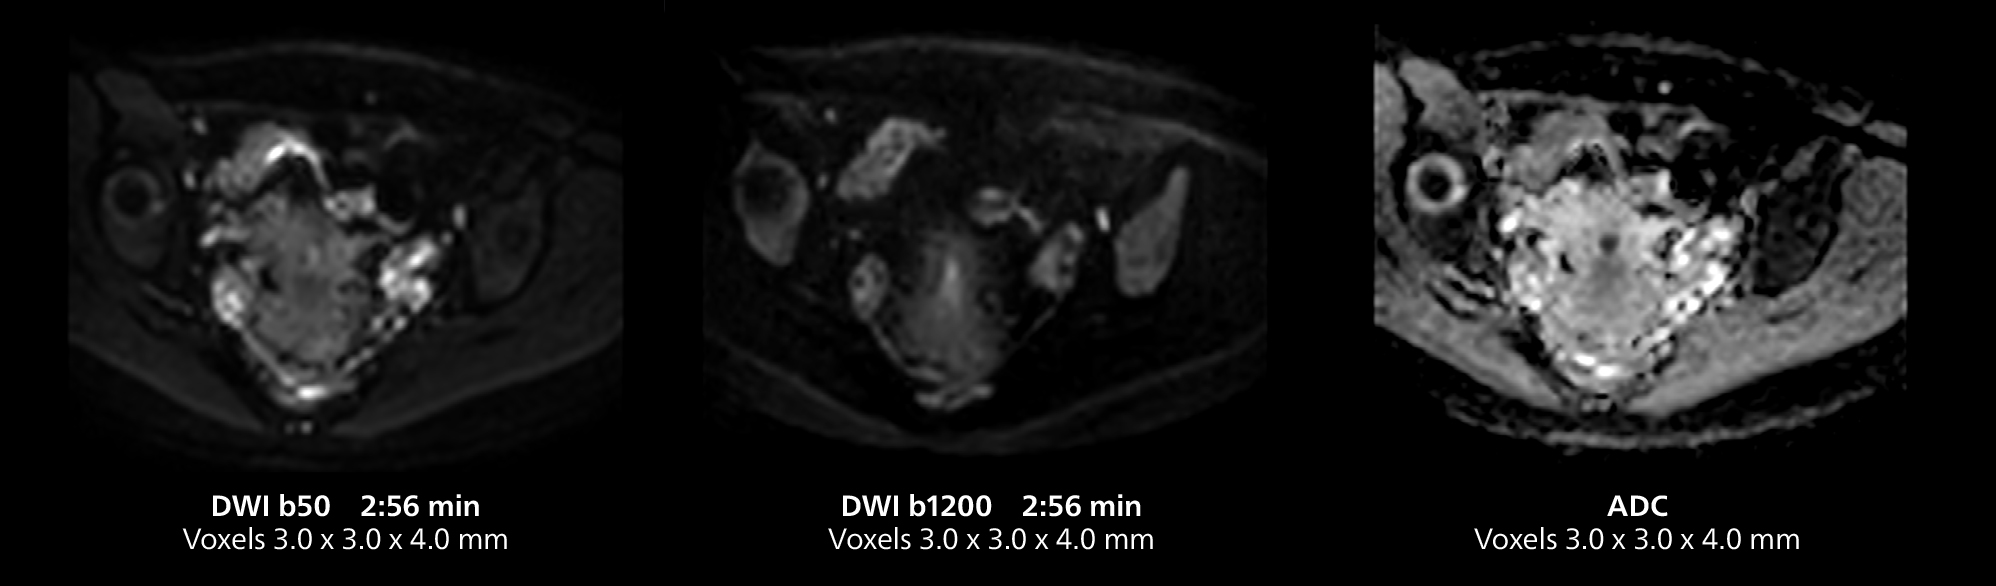

This MRI case illustrates good resolution and imaging quality obtained within reasonable scan times using the MR 5300 1.5T system with the anterior torso cardiac coil that allows use of a large field of view (FOV).

Dr. Gellée highlights the robust free-breathing scans as “the feature that makes the biggest difference in my daily work. The 3D free breathing sequences are very reproducible, and the axial acquisition is very good. For example, in endometriosis, which is one of my focus areas, it provides high contrast and good resolution so that I can see small details. We also use free breathing for liver and pancreas imaging. In multi-phase liver studies, 4D Free Breathing delivers 3-second temporal resolution, making a dynamic scan with more than one arterial phase possible.”